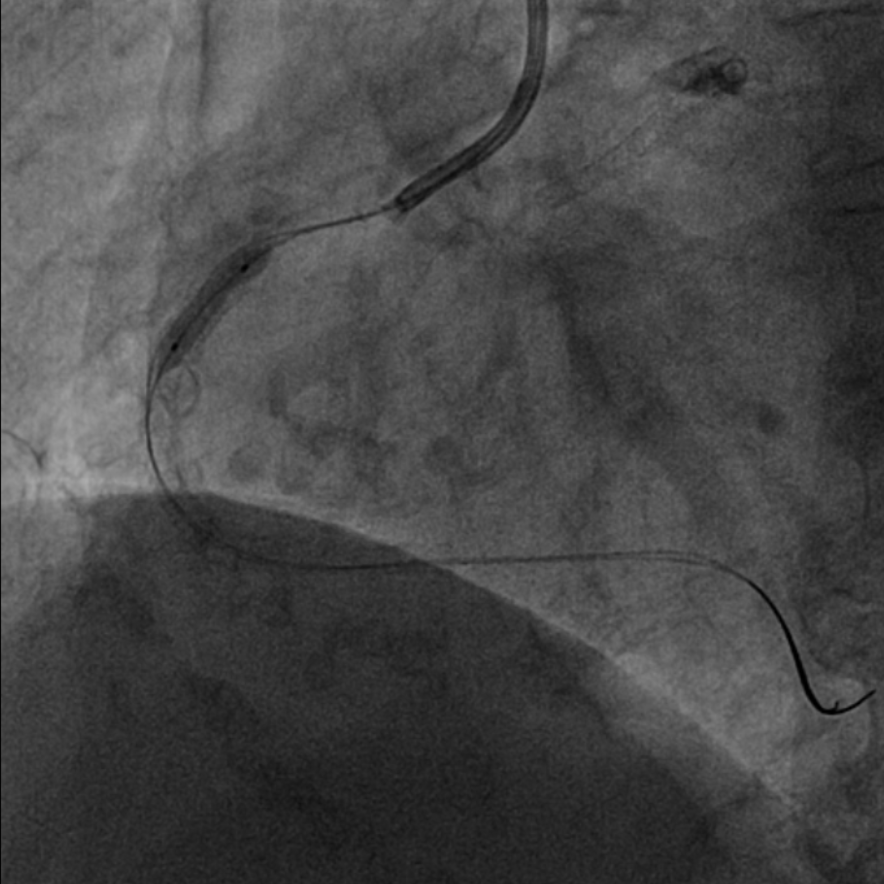

图1 外院手术过程,RCA无法扩张

该患者为68岁女性,14年前于当地医院接受冠脉介入治疗,于左主干至前降支、回旋支及右冠状动脉共植入5枚支架,近10天来再次出现劳力性胸痛,于当地医院造影提示右冠中段支架及左主干支架内再狭窄,回旋支支架内闭塞,由于家属拒绝行CABG治疗,当地医院尝试处理右冠支架再狭窄时球囊未能扩张,为求进一步诊治遂转入西安交通大学第一附属医院心血管内科进一步诊治。